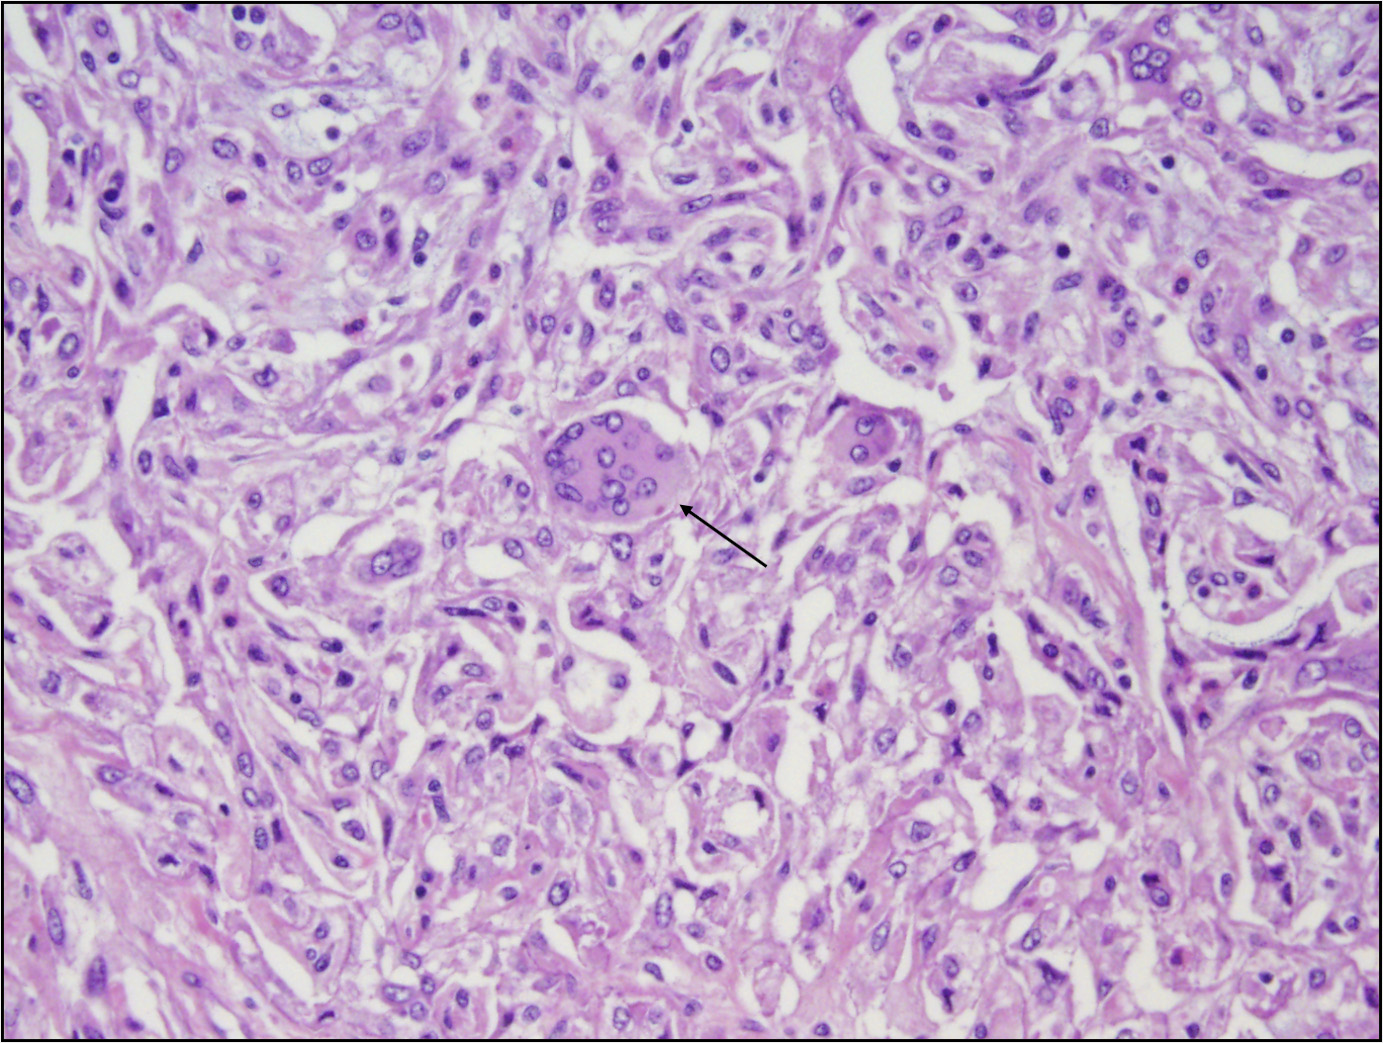

A 55 year old woman without significant medical history was found to have a 2.5 cm mass on mammogram and a biopsy was performed. Histology and immunohistochemical stain for p63 were shown (see images above). What is the likely diagnosis?

H&E section shows a high grade spindle cell lesion with pleomorphic nuclei, irregular nuclear borders and occasional mitotic figures, including atypical mitosis. Based on the morphology, all the listed choices should be considered. Performing a panel of immunohistochemical stains including high molecular weight cytokeratin and p63 is very important and helpful. In this case, the positivity for p63 (as well as other cytokeratins, not shown here) supports the diagnosis of spindle cell carcinoma and makes other choices less likely. It needs to be noted that cytokeratins and p63 are often focal and patchy, therefore a panel of immunostains is usually needed.